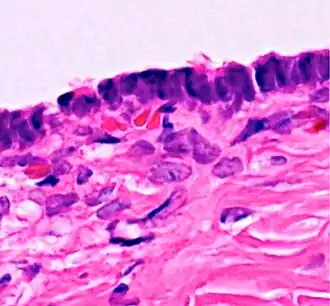

Micrograph of serous carcinoma, a type of serous tumour.